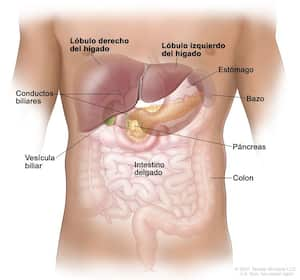

Uno de los tipos de cáncer más comunes es el de estómago, al cual también se le denomina cáncer gástrico o estomacal. Es una enfermedad que se origina en los tejidos que revisten este órgano que se encuentra ubicado del lado izquierdo, en la parte superior del abdomen y que participa en la digestión de los alimentos.

Los expertos explican que el estómago es parte del tubo digestivo, una serie de órganos musculares huecos que forman un tubo largo y retorcido que va desde la boca hasta el ano. El tubo digestivo procesa los nutrientes de los alimentos y ayuda a eliminar los materiales de desecho del cuerpo de la siguiente manera:

- Los alimentos pasan de la garganta al estómago a través de un tubo llamado esófago.

- Una vez que los alimentos y líquidos ingresan al estómago, los músculos del estómago los mezclan con los jugos digestivos para descomponerlos.

- Cuando los alimentos parcialmente digeridos salen del estómago, pasan al intestino delgado y luego, al intestino grueso.

- La porción final del intestino grueso, llamada recto, almacena los desechos de los alimentos digeridos hasta que se expulsan por el ano durante la evacuación intestinal.